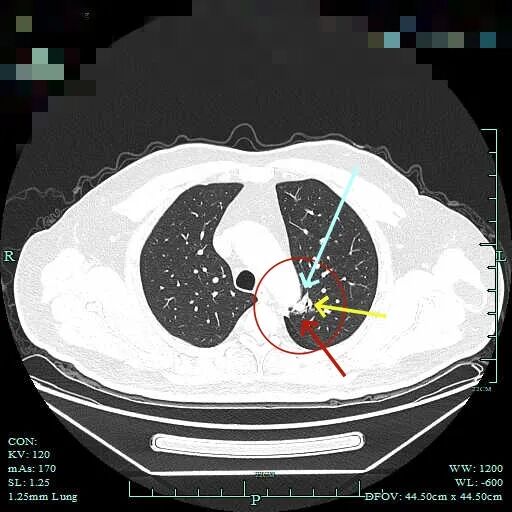

杭州市肿瘤医院影像展示与分析:

右上也有混合密度结节,实性部分缺乏膨胀性与收缩力,磨玻璃成分较淡,也偏糊,但持续存在仍得考虑肿瘤范畴可能性大。

此视角是混合密度,实性为主,贴胸膜近。